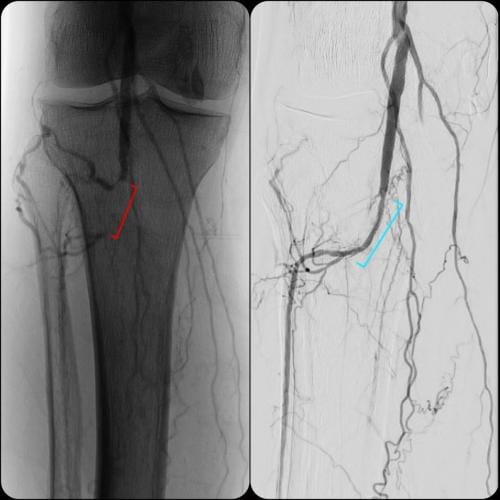

- What is the experience? Choose a specialist that has a proven record of tackling difficult cases successfully. Some specialist choose to only do the simple procedures and refer the rest to surgery. Additionally, if the specialist can only perform simple procedures they may have a higher rate of complication if the case turns out to be more difficult than expected. Our specialist has performed numerous successful complex procedures from the groin, knee and foot. See our prior cases here.

During these procedures: Sedation is given to help you relax. Next, a tiny tube is gently inserted in an artery, usually in the groin or upper thigh area. You will be given a local anesthetic to numb the area where the tube will be inserted. It is then guided through the blood vessel toward the disease artery. When it’s in place, a dye is injected through the catheter to visualize the arteries. An X-ray is taken to help the physician pinpoint the area that is blocked or narrowed. The physician then uses tiny wires and catheters to get through the diseased vessels. Depending on the images treatment may then be performed.

Angioplasty — a special catheter that has a balloon on one end is advanced into the diseased artery. This is temporarily inserted through the narrowed artery and inflated to flatten the plaque against the artery wall, opening the artery and restoring blood flow.

Stent placement —a stent is a small, expandable, leg pain angioplasty stent los Angeles san diegomesh-like tube that supports the artery and helps to keep it open. Implanting a stent does not require open surgery. The doctor inserts a catheter into an artery in your arm or leg, similar to the balloon angioplasty procedure. A specially designed catheter delivers the stent to the narrow area in the artery. The stent is expanded, flattening the plaque against the artery wall and holding the artery open with a mesh tube. The catheter used to deliver the stent is then removed, but the stent stays in your artery permanently to maintain healthy blood flow.

Atherectomy — a specialized catheter that modifies the plaque in the arteries. Unlike angioplasty and stenting, which are designed to move plaque to the sides, atherectomy involves cutting and removing or sanding down the plaque from the artery, restoring normal blood flow.

Superior catheter and wire skills is essential in a delicate procedure such as treating blocked arteries. We treat a number of patients that have had failures by other specialists. Our doctor is an image-guided specialist having performed over 5,000 procedures with successful experience in venous and arterial blockages. Having a wide array of experience in different image-guided procedures brings a unique skill set to ensure that you have the most successful outcome without complication. Rest assured that our specialist can not only complete simple procedures like other centers, but he has a consistent history of successfully treating complex cases.